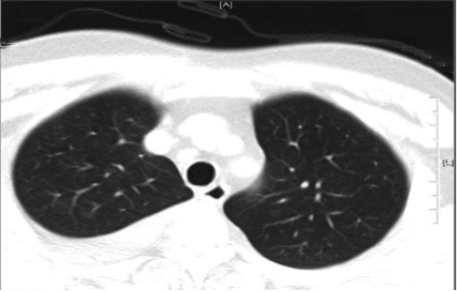

病史摘要:62岁女性,主因鼻塞、咳嗽、流涕伴右侧胁腹痛一周急诊就诊,有2型糖尿病、既往卒中、高血压病史,未接种流感、肺炎球菌及COVID-19疫苗。首次就诊仅接受支持性治疗后出院,一天后因严重右侧胸膜炎性胸痛及右侧胁腹痛再次急诊。 诊疗过程:入院初步检查神志清、血流动力学稳定等,后出现发热等异常。实验室检查白细胞明显升高、乳酸酸中毒,脑脊液中性粒细胞增多等且肺炎链球菌PCR阳性。胸部CTA